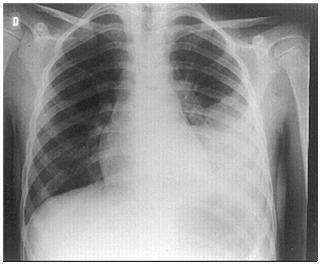

Um homem de 37 anos é internado com febre, calafrios, tosse produtiva e falta de ar de início há 1 dia. Está hemodinamicamente estável, saturando 94% com cateter nasal de oxigênio 2 L/min.

A sua radiografia de tórax mostra:

O tratamento é iniciado com ceftriaxona e claritromicina. Após 24 horas, são identificadas duas hemoculturas positivas para Streptococcus pyogenes. Nesse caso, o tratamento de escolha é